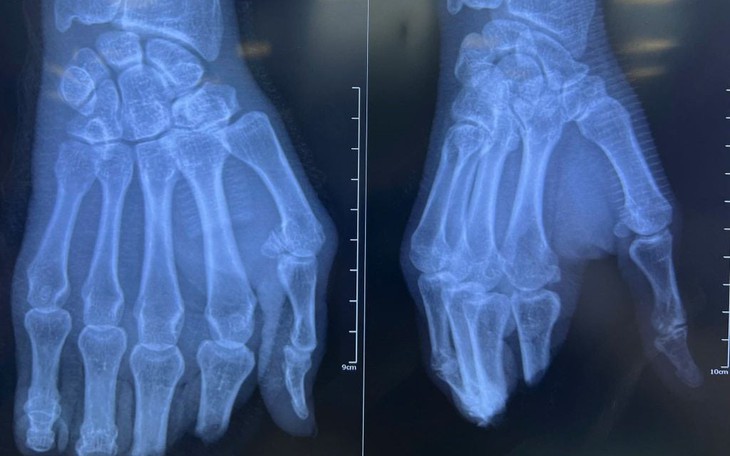

Theo các bác sĩ, đây là ca vi phẫu đặc biệt phức tạp, đòi hỏi tái tạo đồng thời nhiều cấu trúc như xương, động mạch chày trước, chày sau, gân cơ và thần kinh. Thời gian thiếu máu của bàn chân khoảng 2 giờ - nằm trong "thời gian vàng" nhưng ở ngưỡng rất sát, đòi hỏi xử trí khẩn trương, chính xác.

Ca phẫu thuật kéo dài 4,5 giờ, các bác sĩ đã làm sạch tổn thương, cố định xương bằng đinh Kirschner, khâu nối mạch máu để tái lập tuần hoàn, phục hồi gân cơ và thần kinh. Sau khi tái lập dòng máu, bàn chân hồng ấm trở lại.